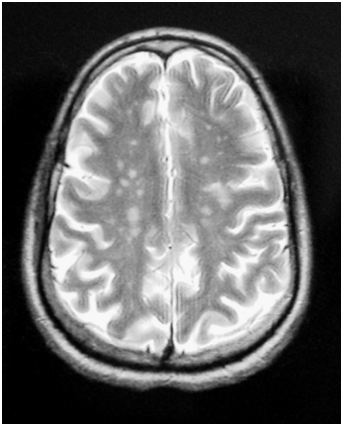

The ophthalmological examination revealed bilateral kerato conjunctivitis with positive Schirmer's and a break-up time tests. The labial minor salivary gland biopsy showed focal lymphocytic sialo adenitis with a focus score at 2. The immunological tests objectified positive anti-nuclear, anti-SSA and anti-SSB antibodies. Brain magnetic resonance imaging (MRI) showed multiple lesions of the periventricular deep white matter and centrum ovale, in T2 and FLAIR hypersignal, T1 hyposignal, and enhancing after Gadolinium injection (Figure 1). Lumbar puncture and cerebrospinal fluid analysis were without abnormalities.

Figure 1 Axial T1-weighted brain MRI with injection: multiple hyper signals of deep periventricular white matter enhancing after Gadolinium.